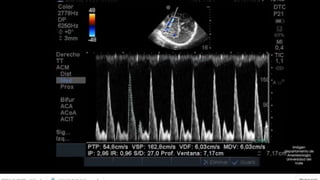

. Monitorización con Doppler trascraneal

• Permite utilizar el ultrasonido para medir la velocidad del torrente

sanguíneo en movimiento, utilizando transductores que emiten y

reciben ultrasonidos con frecuencia conocida.

Mide la velocidad del

flujo sanguíneo cerebral

en los vasos grandes

cerebrales a nivel del

polígono de Willis y sus

ramas.

DOPPLER TRANSCRANEANO